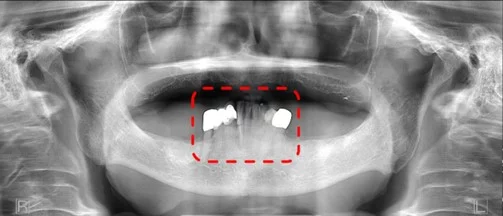

One side of the radiograph is magnified or elongated

If it appears that one side of the patient’s anatomy is stretched or distorted more than the other side, this can point to a patient whose head was not facing straight ahead.

While there are many issues with this image, you can see that one side the mandible is distorted and larger. The corrective action here is to make sure the patient is facing directly forward in the chinrest.